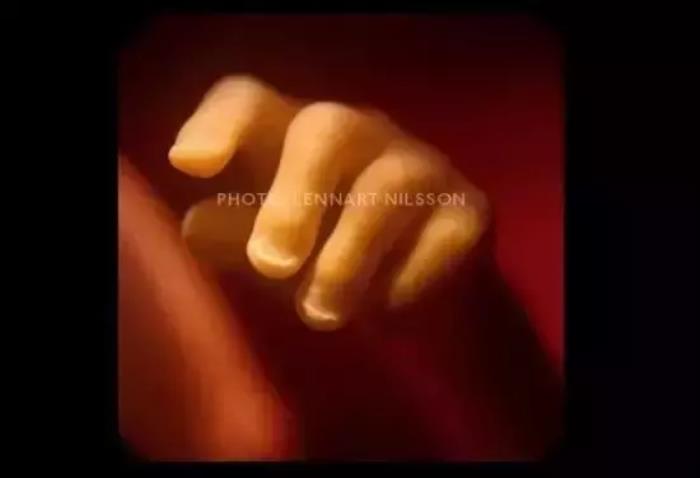

10周。胎儿已经可以使用双手来探索周围的环境